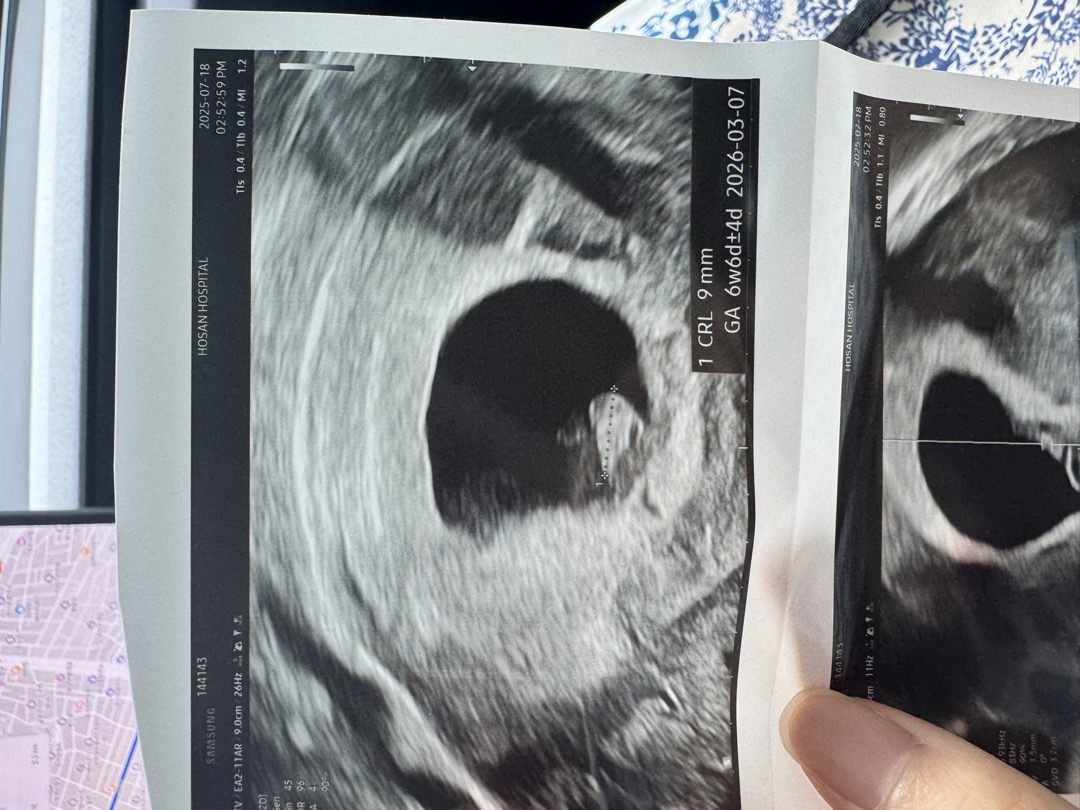

6주6일차 심장소리 듣고왔어요!

지난주 처음 임신 알게되고 동네 병원에서 애기집과 난황 봤었어요. 이후 거의 매일 갈색피가 나서 걱정을 많이 했는데 오늘 처음으로 분만병원 갔더니 다행히 애기 잘 살아있고 심장소리도 들었어요! 약간 꼬물꼬물 움직이면서 심장 뛰는것도 보이더라구요 신기했어요 감동이 될랑말랑..?! ㅋㅋ 생리대 중형 다 젖을 정도 아니면 갈색피는 걱정 안해도 된대요! 근데 저는 물혹이 있어서 운동하면 물혹이 꼬일 수 있다고 가벼운 산책, 요가, 필라테스도 하지 말라고 하시네요ㅠㅠ 가뜩이나 무기력한데.. 입덧약도 하루2알 처방받았어요! 하루종일 입덧 땜에 어기적거리며 다니고 우울하고 토할거같고 한데 그래도 애기가 건강히 잘 자라나고 있다니 다행이네요! 다들 불안하시겠지만 너무 걱정 말고 힘내보아요!!